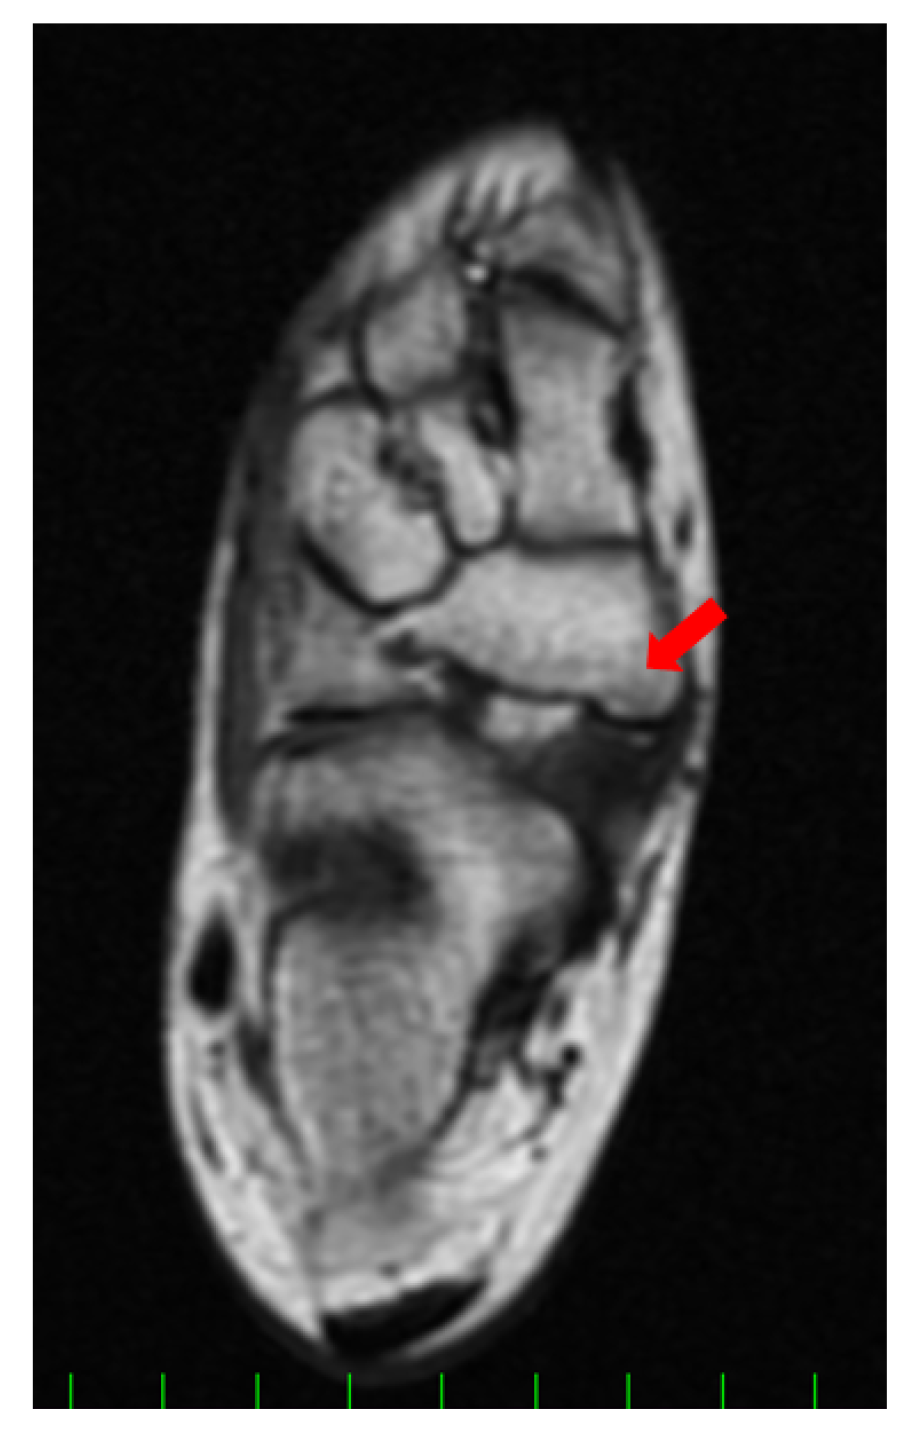

2. Case Presentation